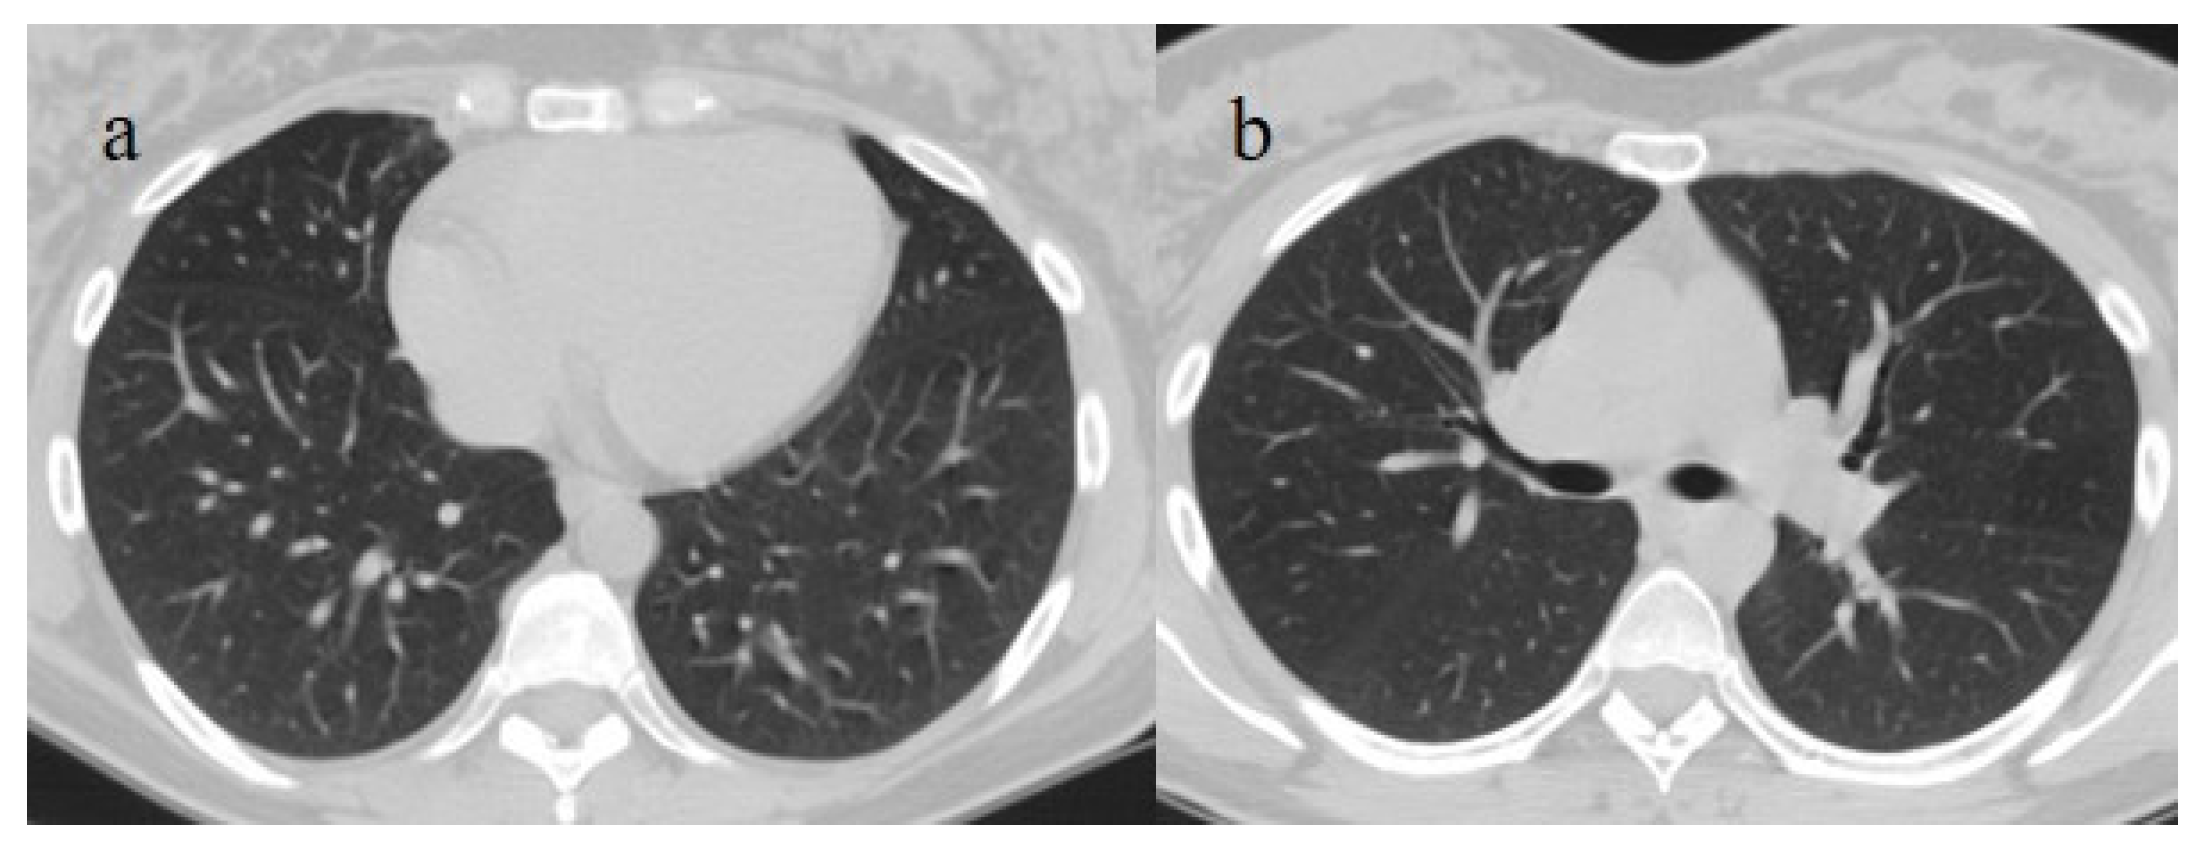

| Typical Appearance | GGOs with a crazy-paving pattern and consolidations in a peripheral and posterior or central-peripheral distribution; multilobar involvement; vascular enlargement, the halo and reversed halo sign; subpleural and parenchymal bands; and architectural distortion. They were predominant since the Delta wave. |

| Indeterminate Appearance | GGOs and consolidations with a unilateral, central, or upper-lobe distribution. |

| Atypical Appearance | Lobar consolidation, lung nodules or masses, miliary patterns, tree-in-bud patterns, cavitation, pleural effusion, central distribution, and lymphadenopathy. Atypical appearances were predominant during the Omicron waves. |

| Typical appearance | From the wild-type to the Delta variant. | Askani et al., 2022 [67] | The Delta variant presented more frequent typical features with more extensive lung involvement than the Omicron variant. The Omicron variant was more frequently associated with the absence of pneumonia. |

| Inui et al., 2021 [68] | Typical findings were characteristic of the wild type to the Delta variant. GGOs with consolidation and repair changes were more frequent in the Delta variant. The Delta variant also showed more rapid pneumonia progression than the wild-type and Alpha variants. | ||

| Ito et al., 2022 [54] | Peripheral GGO distributions were more frequent in the Alpha and Delta variants than the Omicron variant. | ||

| Kirka et al., 2022 [27] | Typical features were found in 40.8% of patients with the wild-type variant and 1.7% of patients with the Omicron variant. | ||

| Lee et al., 2023 [28] | Typical CT patterns were more frequent in the Delta group (76%) than in those with the Omicron variant (42%). | ||

| Yang et al., 2022 [78] | Of patients with the Alpha variant, 86.84% presented typical COVID-19 pneumonia CT features. | ||

| Yoon et al., 2023 [69] | Only 32% of patients with the Omicron variant presented typical findings, compared with 57% of the Delta variant cases. | ||

| Indeterminate appearance | Omicron variant | Ito et al., 2022 [54] | Cluster-like GGOs in the Omicron wave. |

| Atypical appearance | Omicron Variant | Hang et al., 2023 [75] | Patients infected with the Omicron variant presented a significantly higher prevalence of nodules, tree-in-bud patterns, and halo signs than patients with the original strain. |

| Ito et al., 2022 [54] | Prevalence of non-peripheral distribution with random distribution during the Omicron wave. | ||

| Lee et al., 2023 [28] | Peribroncovascular pneumonia with the Omicron variant and lower rates of severe pneumonia than the Delta variant. | ||

| Tsakok et al., 2023 [77] | Patients with an Omicron infection presented a greater frequency of bronchial wall thickening but less severe disease compared with the Delta variant. | ||

| Yang et al., 2022 [78] | Only 1.3% of patients infected with the Omicron variant had foci of pneumonia, and the GGOs were unilateral and centrilobular. | ||

| Yoon et al., 2023 [69] | Peribroncovascular GGOs or centrolobular foci during the Omicron wave with less extensive pneumonia. |